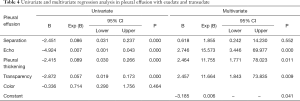

The regression equations for the pleural effusion with exudate and transudate are shown in Table 4.

Full table

Binary logistic regression analysis was performed with exudates and transudates as the dependent variables and the above characteristics as the independent variables, and the results are shown in Table 4. Pleural thickening, transparency, and echo can be used as independent variables to establish the model (P=0.034), and the equation for the model was as follows:

The G-test was used in the logistic regression with a G-value of 11.028, and a P value of 0.004. Using this logistic regression model, patient prognosis was predicted by P values calculated in logistic regression, and the predictive accuracy was 76.2%. The area under the receiver operating characteristic (ROC) curve (AUC) for pleural thickening was 0.762 (95% CI: 0.660–0.864, P=0.000), the sensitivity was 69.1%, and the specificity was 83.3%. The AUC for transparency was 0.806 (95% CI: 0.710–0.903, P=0.000), the sensitivity was 77.9%, and the specificity was 83.3%. The AUC for echo was 0.910 (95% CI: 0.838–0.981, P=0.000), the sensitivity was 94.1%, and the specificity was 83.3% (Figure 4).